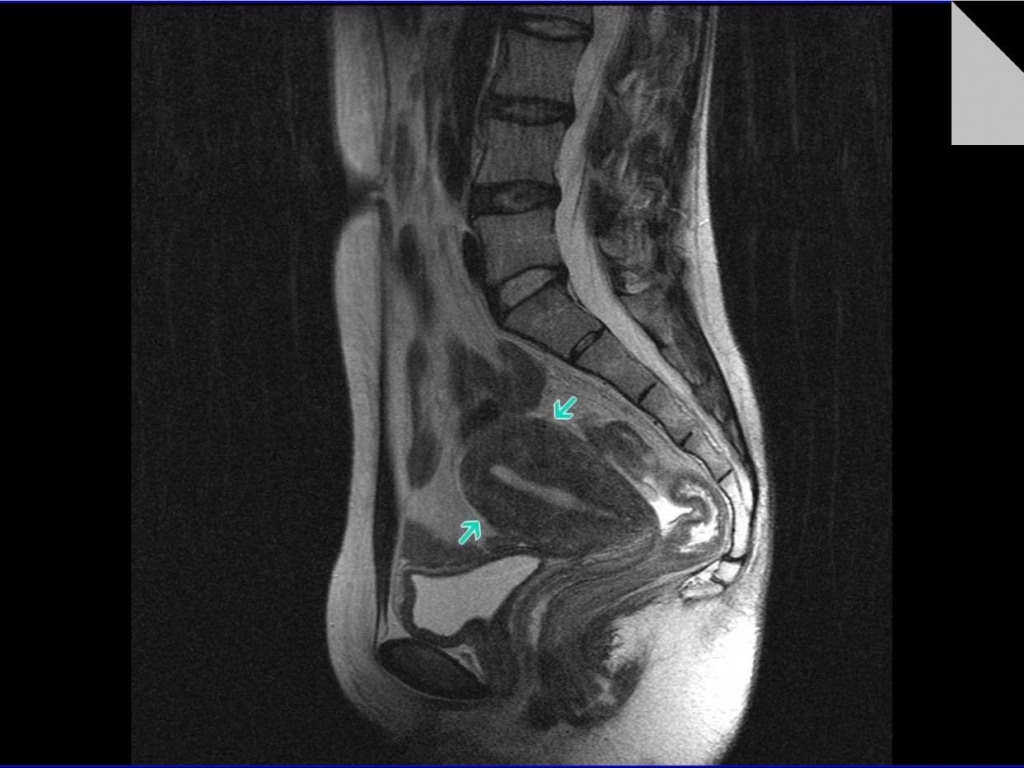

МРТ органов брюшной полости.